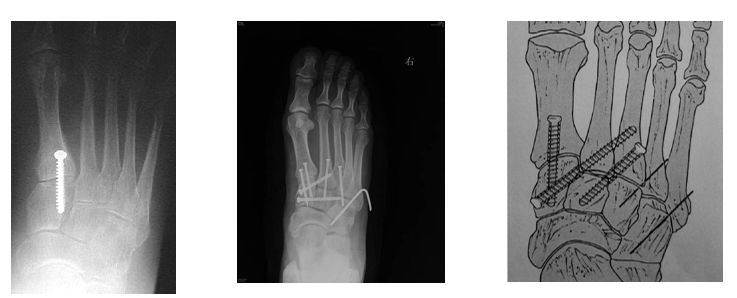

内固定选择1、克氏针:优点是手术简单、时间短、对周围组织损伤小,缺点是固定不坚强、复位丢失等情况时有发生。2、可吸收螺钉:优点是不需行二次手术取出内固定物,缺点是固定强度不及传统螺钉3、小螺钉系统:经典 --- 3.0mm、3.5mm、4.0mm4、空心螺钉:3.0mm、4.0mm、4.3mm 、4.5mm5、微型钢板:跨关节固定,对于严重的跖骨粉碎性骨折的患者,螺钉无法固定时,建议选择微型钢板桥接固定6、骑缝钉

手术切口选择单一切口、双切口

双切口能充分显露所有的跖跗关节;第一切口位于第一、二跖骨之间。该切口利用了两个间隙,一个拇长伸肌腱内侧,一个为拇短伸肌腱外侧。分别可显露第一跖骨、内侧楔骨和第二跖骨、中间楔骨。通过延长皮肤切口,可以直视第三跖骨和外侧楔骨。第二切口位于第四、五跖骨之间,可以显露其与骰骨之间的关节。

根据三柱理论1、首先复位内侧柱并临时固定 2、再复位固定中间柱3、如外侧柱移位可能需双切口

手术从第一跖骨和内侧楔骨开始。首先直视下复位该关节,评价楔骨之间的稳定性,关节囊通常撕裂,但仍然需要掀开以充分显露关节,清除关节内的软组织和软骨碎片。

内侧柱稳定后,开始处理第二跖骨和中间楔骨。点式复位钳由第二跖骨基底部外侧远端斜向内侧楔骨内侧面的近端夹持,注意避免第二跖骨向下移位,发生复位不良。

若楔间关节仍不稳,可使用楔骨间螺钉;固定内侧两跖骨后,通常第三跖骨已经足够稳定,若仍未复位,可以参考第一跖骨固定方法固定。通过第二切口固定第4、5跖骨。可以使用克氏针固定。

Lisfranc损伤骨折复位标准:1、C形臂透视显示正、侧、斜位均为正常解剖复位2、如复位后第1、2跖骨基底间隙和内、中楔骨间隙<2mm,跖跗骨轴线<15°为近解剖复位,可以接受,超过这个范围的移位则无法接受3、复位好后,沿第一跖骨轴线向内侧楔骨逆行拧入一枚4.0mm皮质骨螺钉。螺钉由关节远侧1.5-2.0cm处进入,平行于足底或略向跖侧。

4、从内侧楔骨向第二跖骨置入一枚螺钉,重建韧带。螺钉自内侧楔骨近端的背侧置入,指向第二跖骨背侧皮质的下方,螺钉应通过4层皮质,确保对第二跖骨的双皮质固定